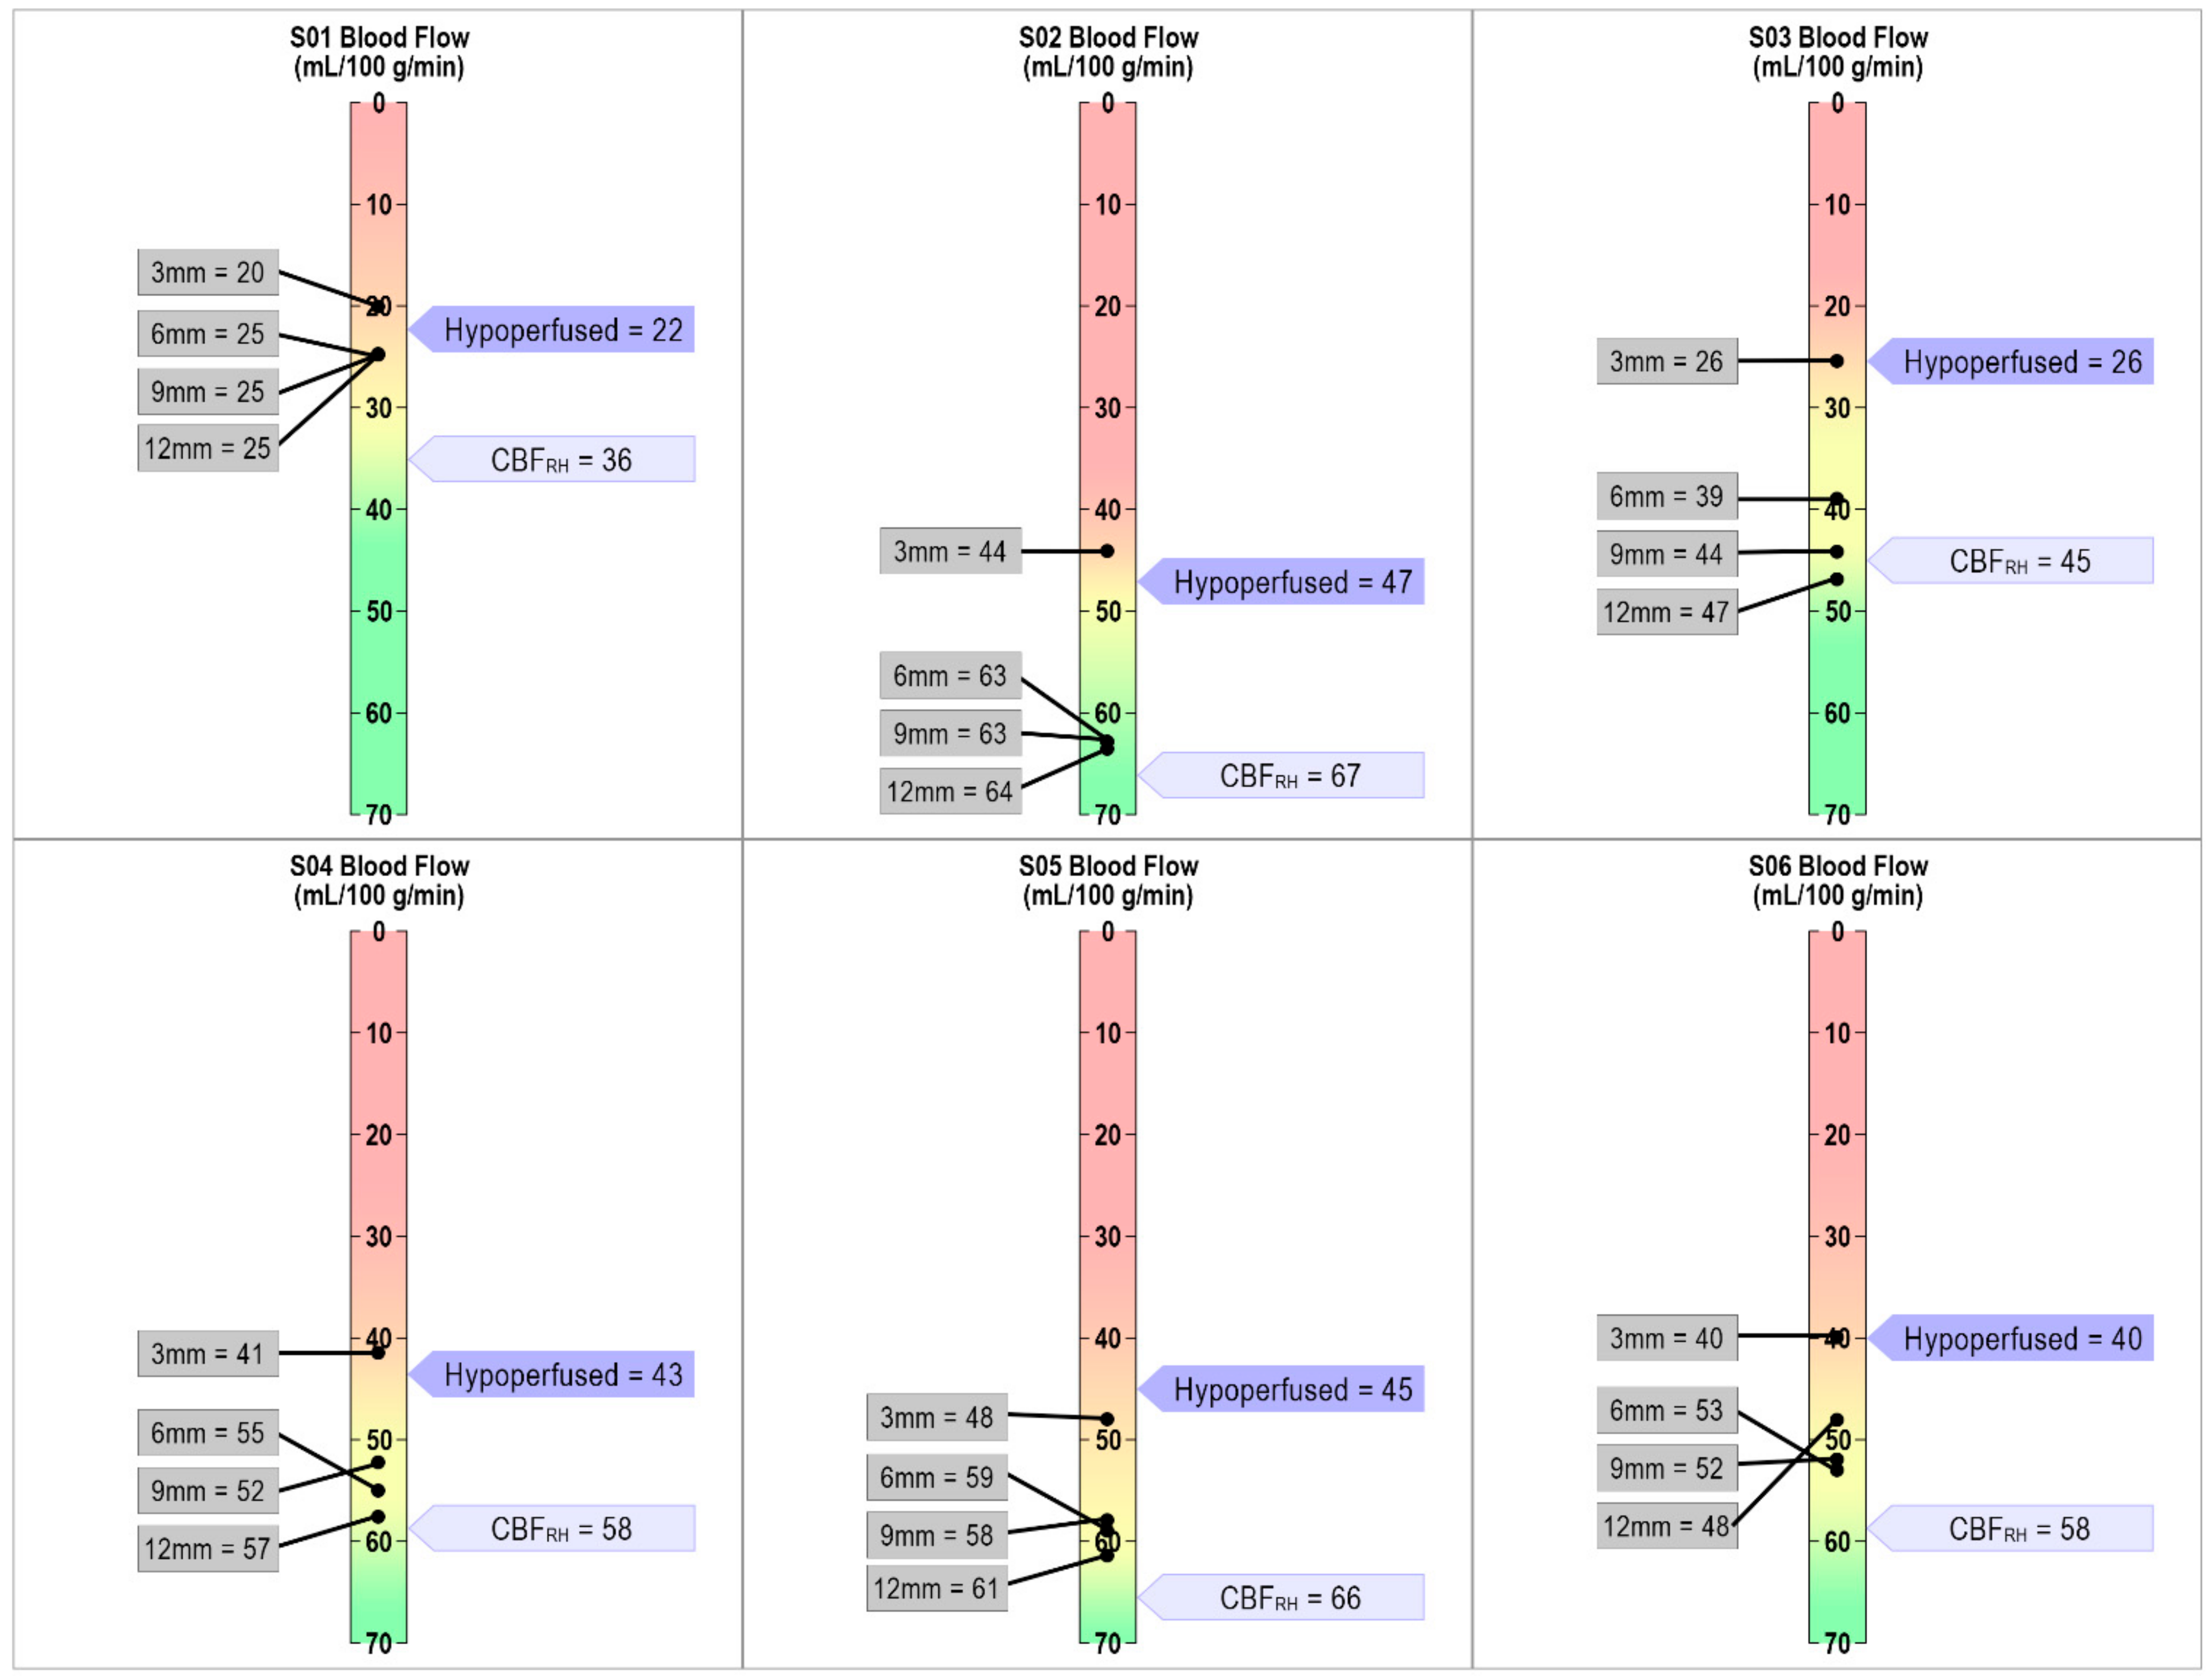

4.4. Defining Hypoperfusion within Perilesional Rings: Individualized Thresholding

4.5. Identifying Hypoperfused Tissue in Language Regions

Appendix A. Perilesional Masks: Left Hemisphere Versus Right Hemisphere